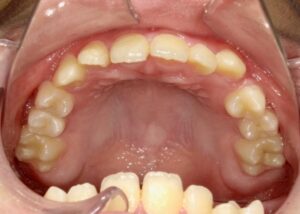

上顎

- Before